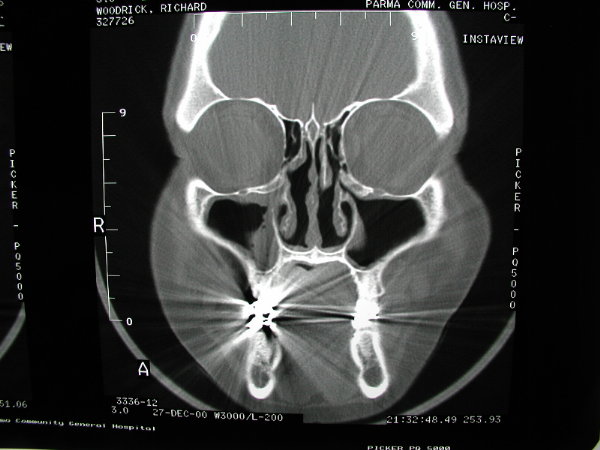

The patient above had a fascinating CT scan.  He basically has no nasal floor, as the maxillary sinuses extend below his nasal cavity, and replace his hard palate.  His sinus surgery was surprisingly straight-forward and he healed rapidly.